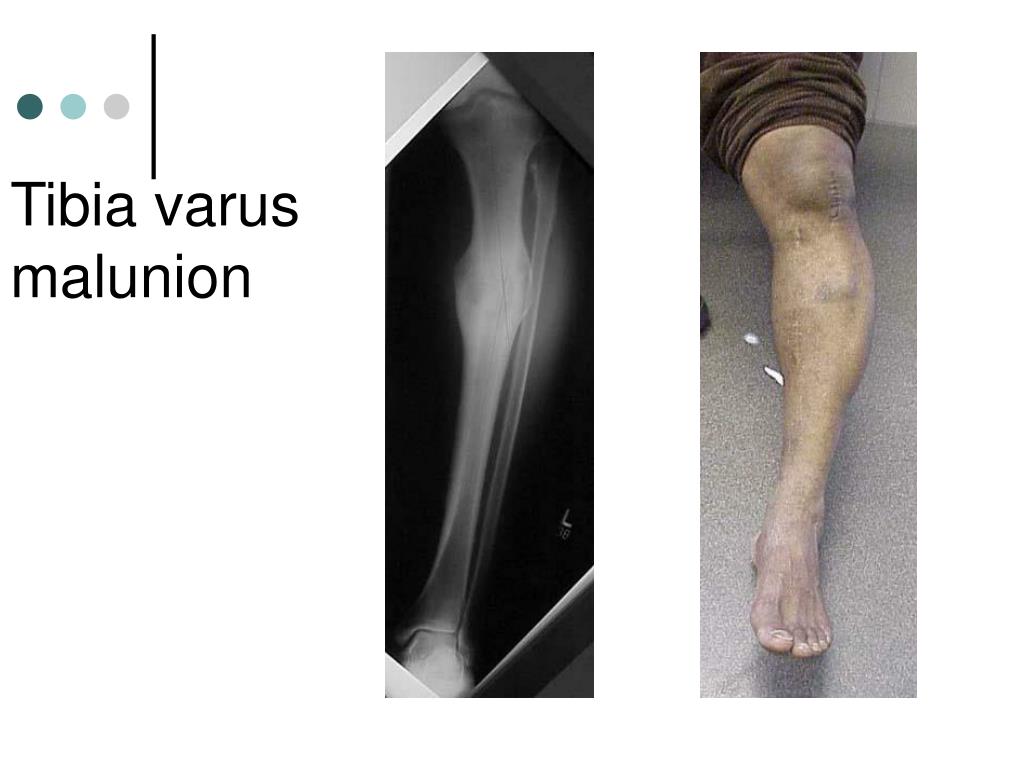

6. Gróning beinbrota • Brot sem eru ekki meðhöndluð geta: • Gróið saman eðlilega • Gróið saman seint (delayed union) • Gróið saman í rangri stöðu (malunion/cross union) • Nær ekki að gróa saman (nonunion)

7. Tibia varus malunion